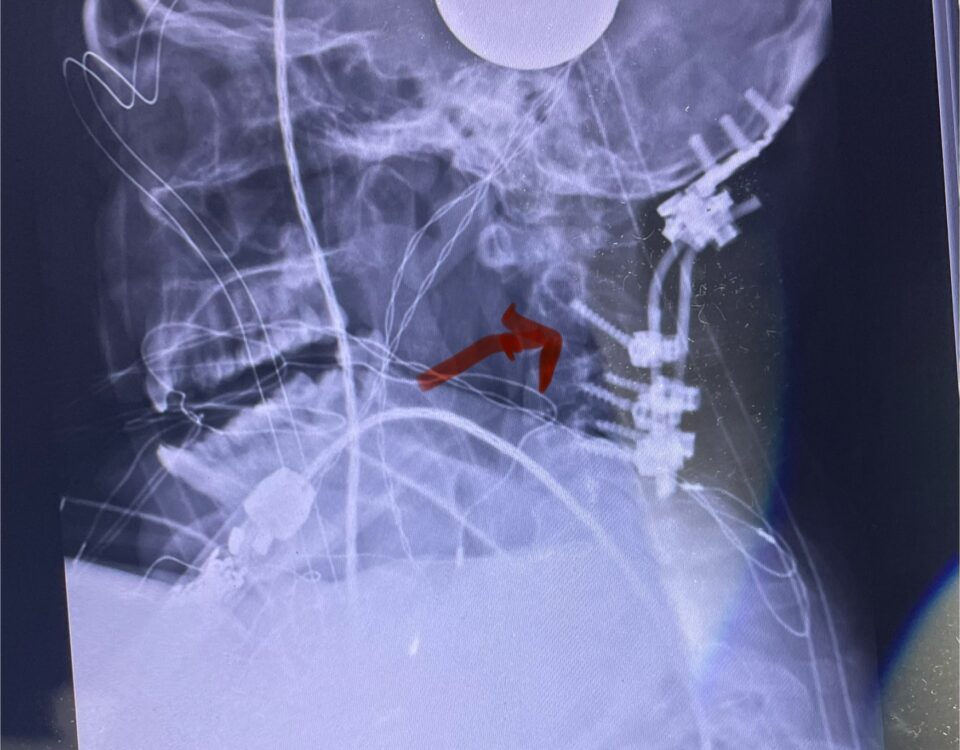

As a spine surgeon you see patients with all body types. Morbidly obese patients pose a particular challenge. Heavy patients who have lumbar spinal stenosis or […]